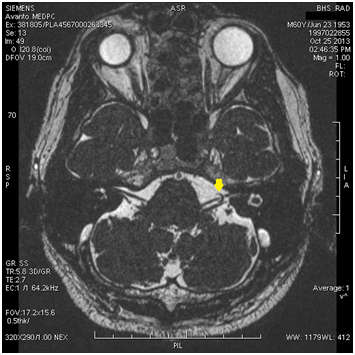

After a 9‒month asymptomatic period, the patient presented at our clinic with an electric‒shock like pain that could be provoked by light touch to the preauricular area. Patient history and physical examination revealed that the pain was aggravated in association with the elevation of the blood pressure, anxiety and tiredness. Then the patient was referred to the cardiology department and diagnosed with essential hypertension. Cranial MRI was repeated for a detailed examination and revealed a vascular loop that was contacting to the left trigeminal root exit zone (Figure 1). The hypertension was treated and the patient was encouraged to make lifestyle modifications and the control of hypertension was achieved. After the control of blood hypertension, complete resolution of symptoms were observed at 1‒month and 3‒ months follow up. Unfortunately we weren’t able to obtain a control MRI for economical reasons. At 5 years of follow –up the patient patient remains pain free. We considered unstable blood hypertension seemed to contribute to the exacerbation of his neuralgia in the presence of a vascular loop contacting to the trigeminal root exit zone. After the control of blood hypertension, spontaneous recovery of neuralgia was observed.

Figure 1 Vascular loop contacting to the left trigeminal root exit zone.